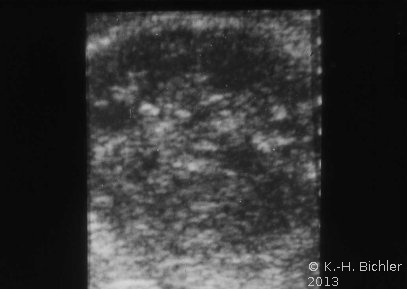

Von Wichtigkeit sind die bildgebenden Verfahren: Sonographie, CT bzw. AUR.

Beispielhaft die Darstellung eines ausgedehnten Nierenabszesses in Sonographie, CT und AUR (Abbildung 6).

Die Abbildung zeigt als weiteres Beispiel die sonographische Darstellung eines ausgedehnten paranephritischen Abszesses (Abbildung 7).